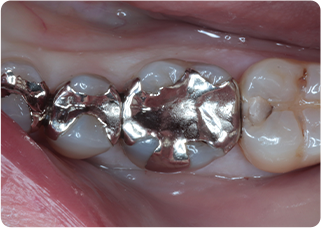

精密根管治療②

術前

術後

| 主訴 | 奥歯で噛むと痛い |

|---|---|

| 治療期間/回数 | 1ヵ月、3回 |

| 価格(税込) | 88,000円(税込) |

| リスク・副作用 | 病変再発、歯根破折の可能性 |

| ポイント | う蝕検知液を用い、むし歯の取り残しが無いようにし、ラバーダム防湿を行い、無菌的に根管治療を行った。根管充填材は、殺菌作用の強い保険適応外のMTAセメントを使用した。 |